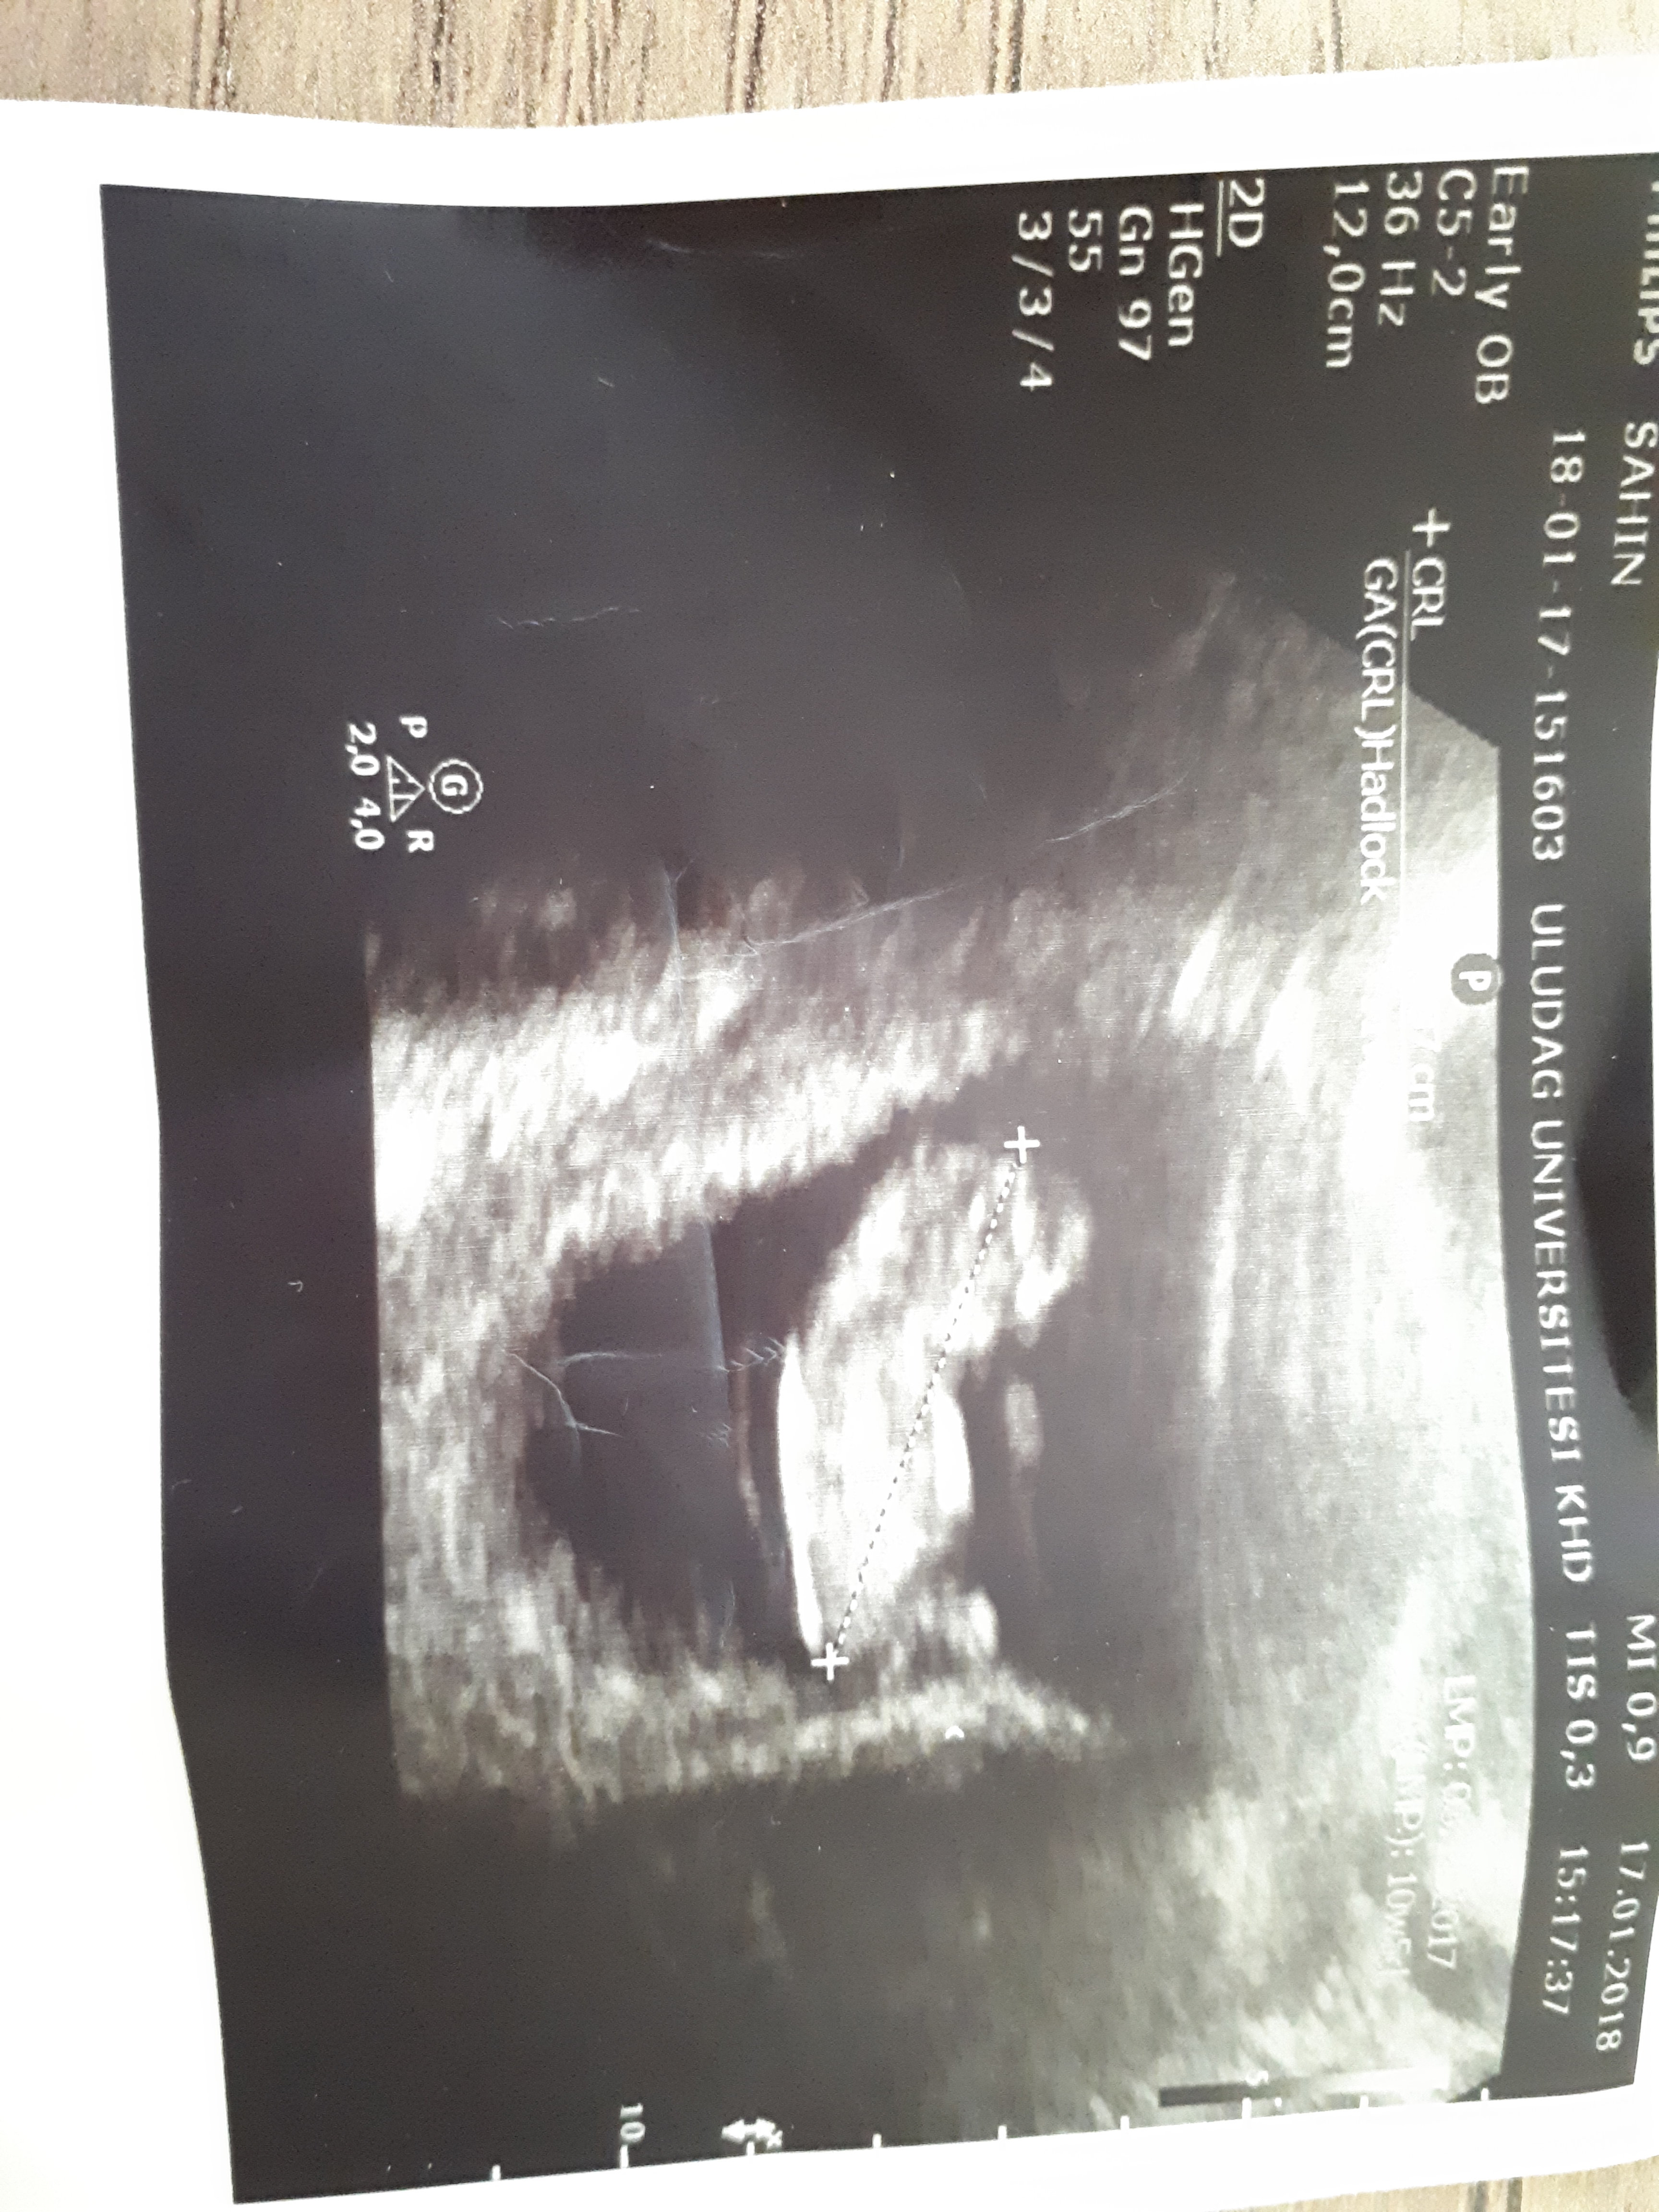

Birde şu görüntü var bunda peki bellimi ama burada 11 haftalikMerhaba canım bebeğinin pozisyonundan dolayı nub çıkıntısı görünmüyorki